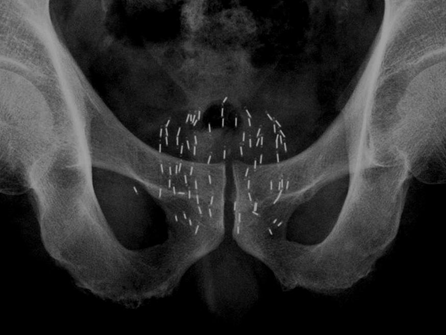

- 放射線療法 (放射線療法):この方法では高エネルギービームを使用し、腫瘍を縮小することもできます。放射線療法は、化学療法治療中または化学療法治療後に使用される場合があります。これは、前立腺がんが体の他の部分に転移している場合に特に役立ちます。

- 手術:進行した場合には、前立腺の外科的除去(根治的前立腺切除術)と片方または両方の睾丸が必要になる場合もあります。